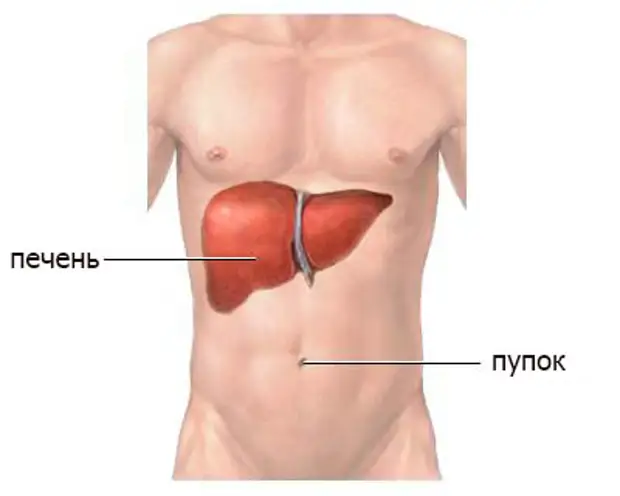

Анатомия желудка и сердца: визуализация и изучение

Раздел: Фотопанорама